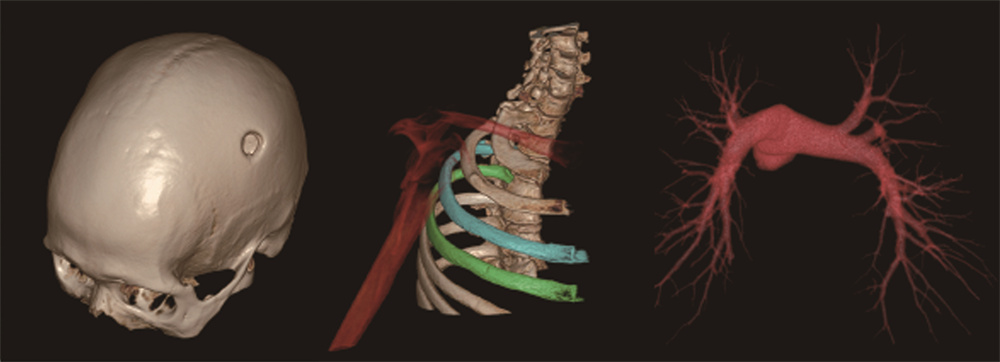

“高精尖”医疗设备,为诊疗步伐按下“加速键”,先进的医疗设备是医院高质量发展的硬核保障。寿光和信医院联影640层高端CT在临床诊断中发挥了重要作用,为大量患者提供了快速、高效、智能的检查服务,尤其在心脑血管疾病、急危重症等领域,提供了精准的影像信息。这种技术进步不仅提升了诊断的准确性,也为国家推动的胸痛中心、脑卒中中心、肿瘤中心和创伤中心的建设提供了有力支持。

联影640层CT是中国CT届的“天花板”,集当今CT领域的顶尖科技于一身,将各项临床应用发挥到极致,为患者带来精准、舒适、安全的CT检查新体验。建立了心血管、神经、肿瘤、呼吸系统、泌尿系统及骨科专业等疾病的成像和低剂量筛查领域全新标准,真正实现全方位成像,结合AI人工智能技术,提高疾病诊断率。

凭借先进硬件平台和独有的AI冠脉追焦技术,不管是对于严重心律不齐、房颤、房扑,还是超高心率等一般CT做不了的心脏检查的情况,联影640层CT都可以获得高清的成像效果,助力精准临床诊断。

联影640层CT采用宽体采集,一次检查即可获得全脑平扫图像、动静脉造影图像和灌注图像,不仅可应用于急诊缺血性脑卒中的影像评估,还可助力脑血管畸形、脑动脉瘤等其他脑血管病的结构和功能评估。

针对胸痛、脑出血、外伤、急腹症等多种急诊检查场景,联影640层CT提供全速急诊方案,检查时间最短化,图像评估直观化,为生命争分夺秒。